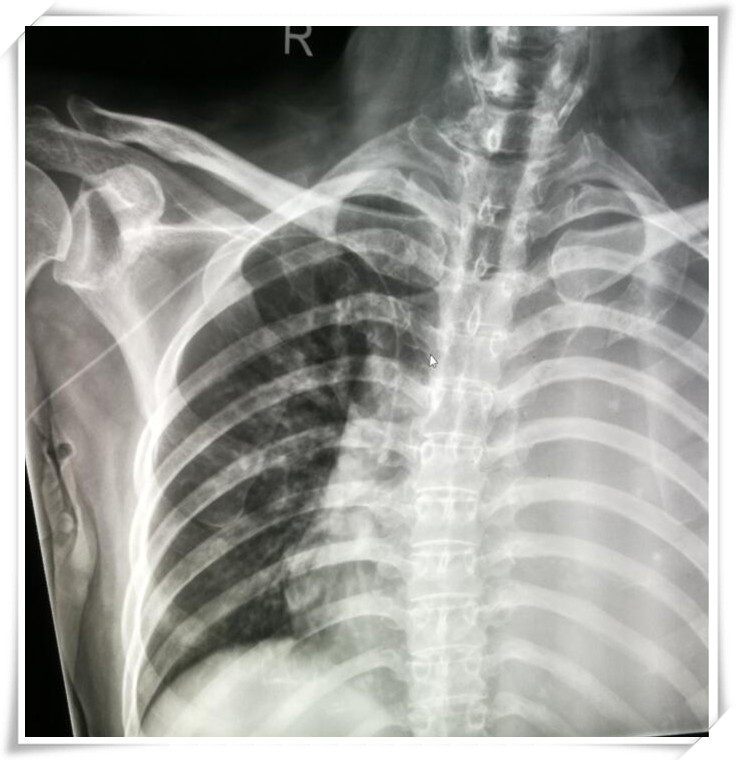

患者置管后影像资料▼